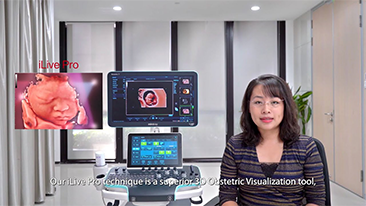

?QuĂ© tan claramente se puede ver un hĂgado?

Para las lesiones hepĂĄticas focales, como el hemangioma o el cĂĄncer de hĂgado, el diagnĂłstico por imĂĄgenes mediante ecografĂa con contraste cumple un papel importante. La tecnologĂa de diagnĂłstico por imĂĄgenes con contraste UWN+ (no lineal ultraancha) puede ayudar a obtener una mejor penetraciĂłn, una mayor relaciĂłn contraste-tejido, con un IM mĂĄs bajo y una observaciĂłn del tiempo de perfusiĂłn mĂĄs prolongada.